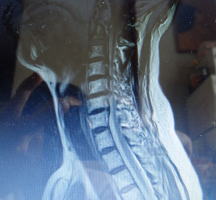

| 手術後の画像 |

ボルトの入った 状態の画像と 思うのですが? |